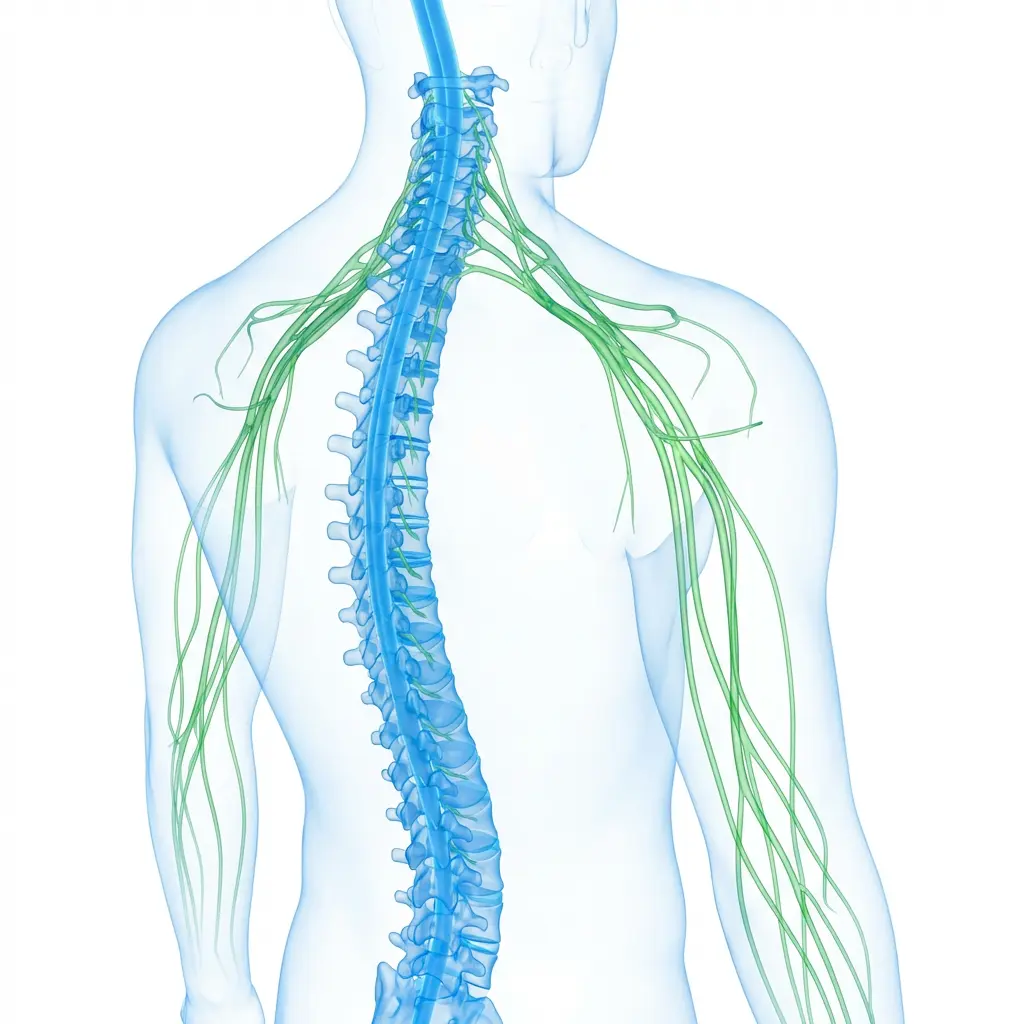

As a specialist in Functional Neuromodulation Surgery, he offers advanced treatments including Deep Brain Stimulation (DBS) for Parkinson’s disease, epilepsy surgery, and procedures for chronic neurological conditions. He is among the first neurosurgeons in Gujarat to develop expertise in this highly specialized field.

Dr Chirag Solanki, the best Neurosurgeon in Gujarat as expertise in treating a wide range of neurological conditions, including brain strokes, aneurysms, brain tumors, Parkinson’s disease, tremors, dystonia, epilepsy, pain, incontinence, psychosurgeries, spine problems and spinal tumors and traumatic brain injuries. We also offer comprehensive care options, from minimally invasive procedures to complex surgical interventions.